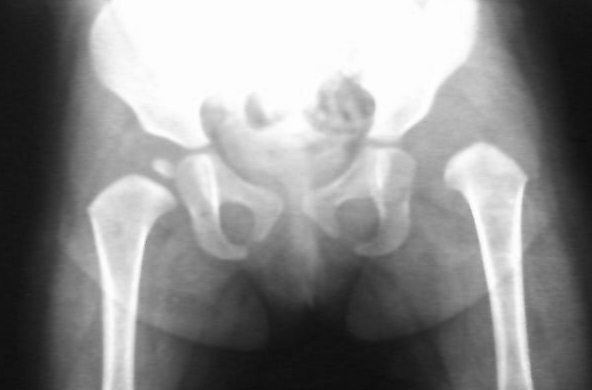

先天性左侧髋关节脱位。

考虑左髋关节先性脱位。

左侧先天性髋关节脱位.

左侧先天性髋关节脱位.典型!